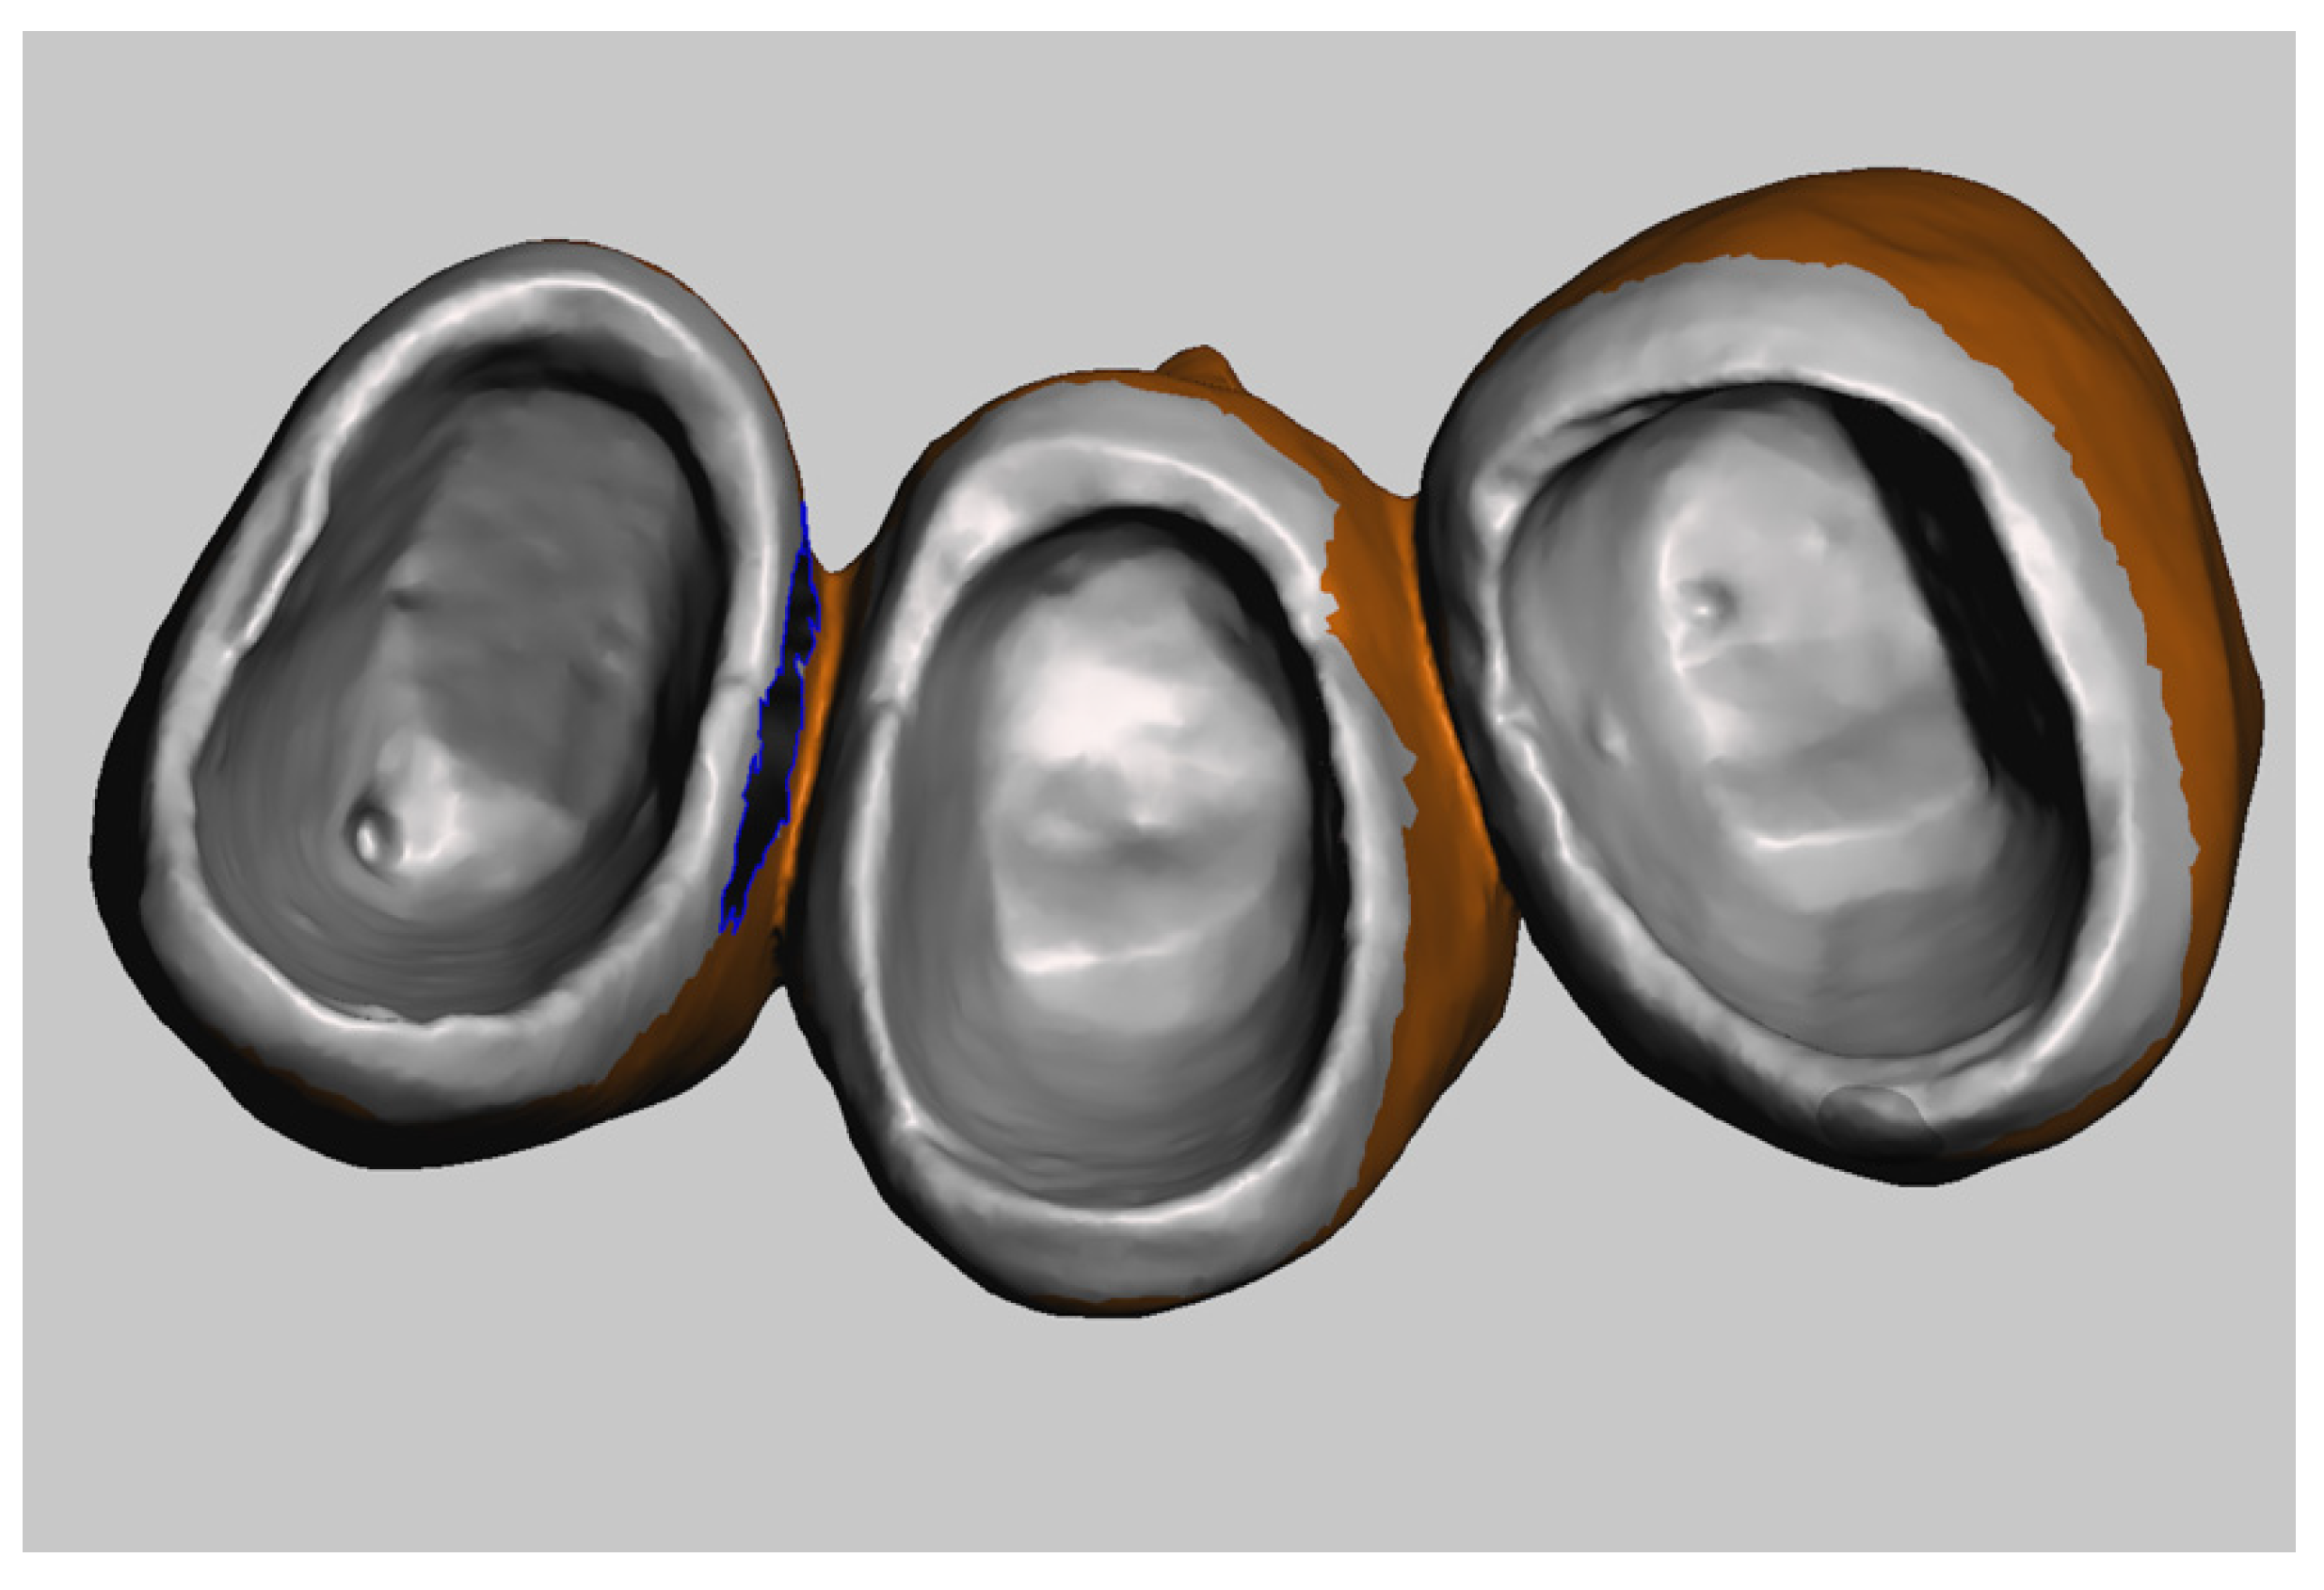

- Step A: Cleaning STL Files

The first step is to prepare impression files suitable for subsequent steps. After importing the scan of the abutments and the provisional restoration into MeshMixer, we select and delete all of the unnecessary triangles of the mesh using the tool “Delete”. In the abutments scan, it is mandatory to maintain information related to tooth preparation. The buccal and lingual sides are minimised and the teeth adjacent to the preparations are removed (Figure 7). The provisional restoration scan provides information on the emergency profile and finish line of the crown, and therefore the cervical part and the inner side of the crown are carefully maintained (Figure 8). Because the scan represents the negative of the abutment, the next step is re-orienting the triangles of the STL file. This manipulation is performed via the command “Flip Normal”, after selecting the entire mesh surface (Figure 9).

Figure 7.

Digital impression of the abutments.

Figure 8.

Selection of unnecessary areas.

Figure 9.

Manipulation of the inside area of the provisional restoration after deleting all unnecessary areas.